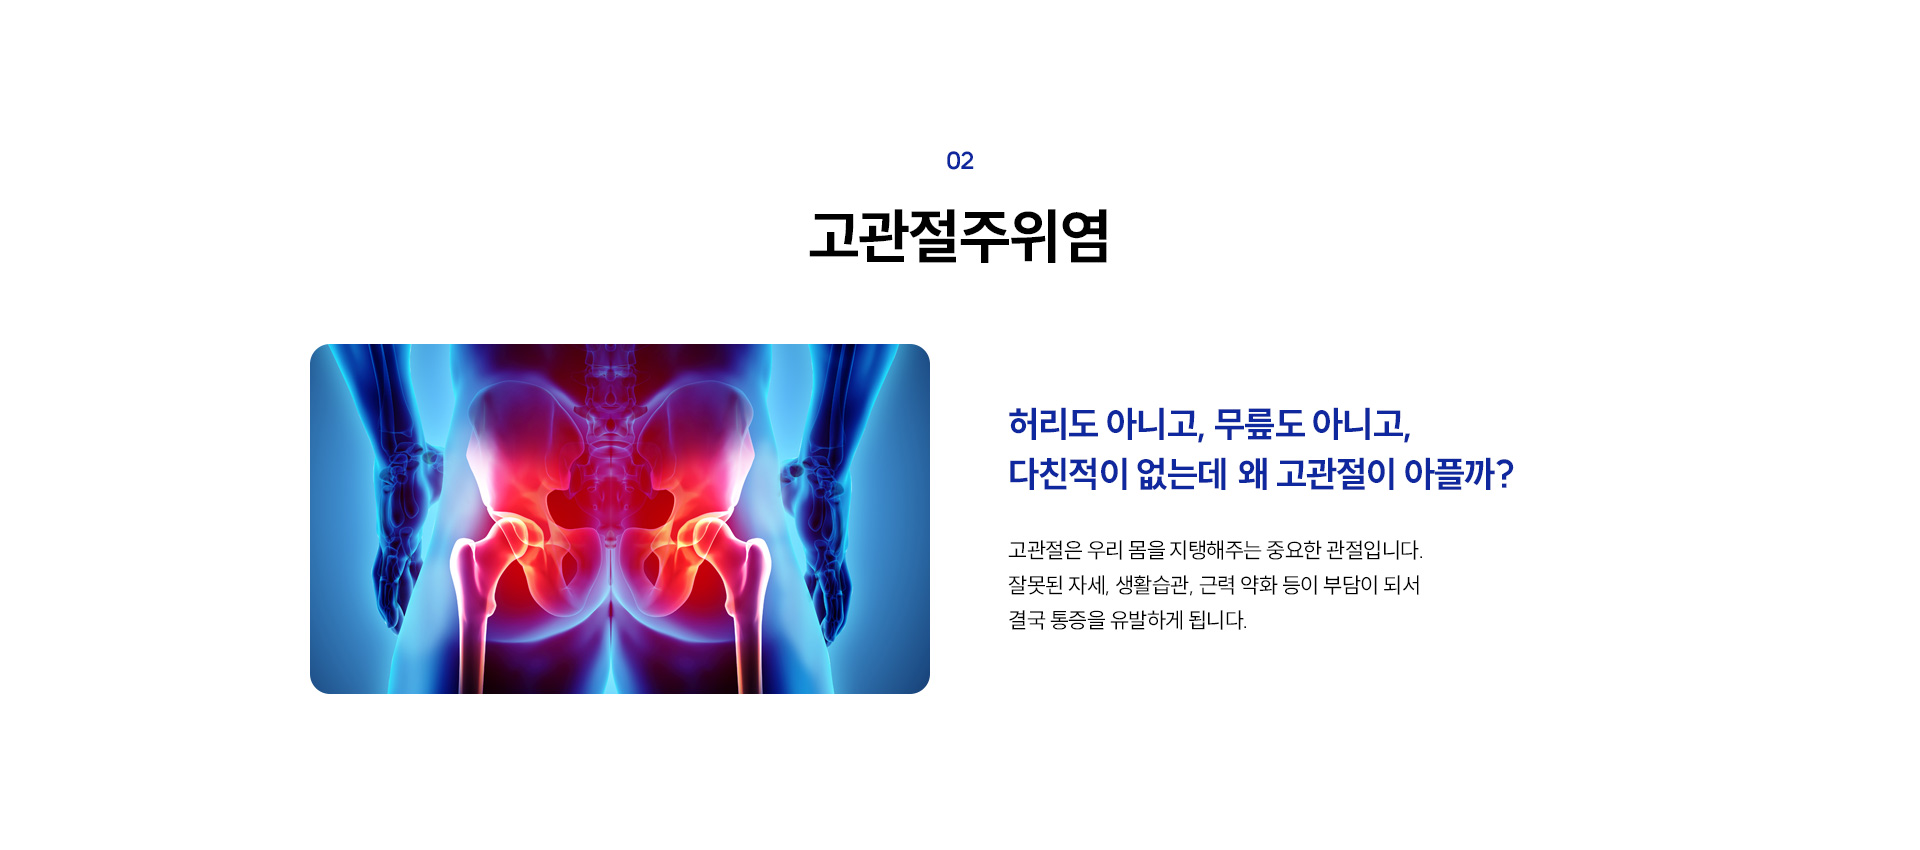

기운찬이 알려주는 고관절주위염에 대한 자주 묻는 질문 Q&A

고관절을 둘러싼 근육과 힘줄이 약해지거나 무리하게 사용되면 염증이 생기기 쉽습니다.

특히 오래 서 있거나, 한쪽 다리에 체중을 실는 자세, 다리를 꼬고 앉는 습관, 쪼그려 앉는 동작을 반복하는 경우

고관절에 과도한 부담이 가해져 염증이 유발될 수 있습니다.

50대 이상에서는 자연스럽게 근육과 힘줄이 약해지기 때문에 고관절염증이 더 쉽게 발생할 수 있으며, 젊은 연령층이라 하더라도

초기에는 허벅지, 엉덩이, 무릎 주변에 가벼운 뻐근함이나 불편감이 나타날 수 있습니다.

하지만 증상이 점차 악화되면, 오래 서 있거나 걸을 때 통증이 심해지고, 보행 시 자세가 비대칭적으로 무너지는 현상이 나타날 수 있습니다.

또한, 고관절의 불균형이 요추 디스크 탈출(허리디스크)에도 영향을 줄 수 있으며, 염증이 지속되면 야간 통증으로 인해 숙면이 어려워질 수 있습니다.

혈액순환까지 저하될 경우, 드물게는 무혈성 괴사로 진행될 가능성도 있어 조기 진단과 치료가 매우 중요합니다.